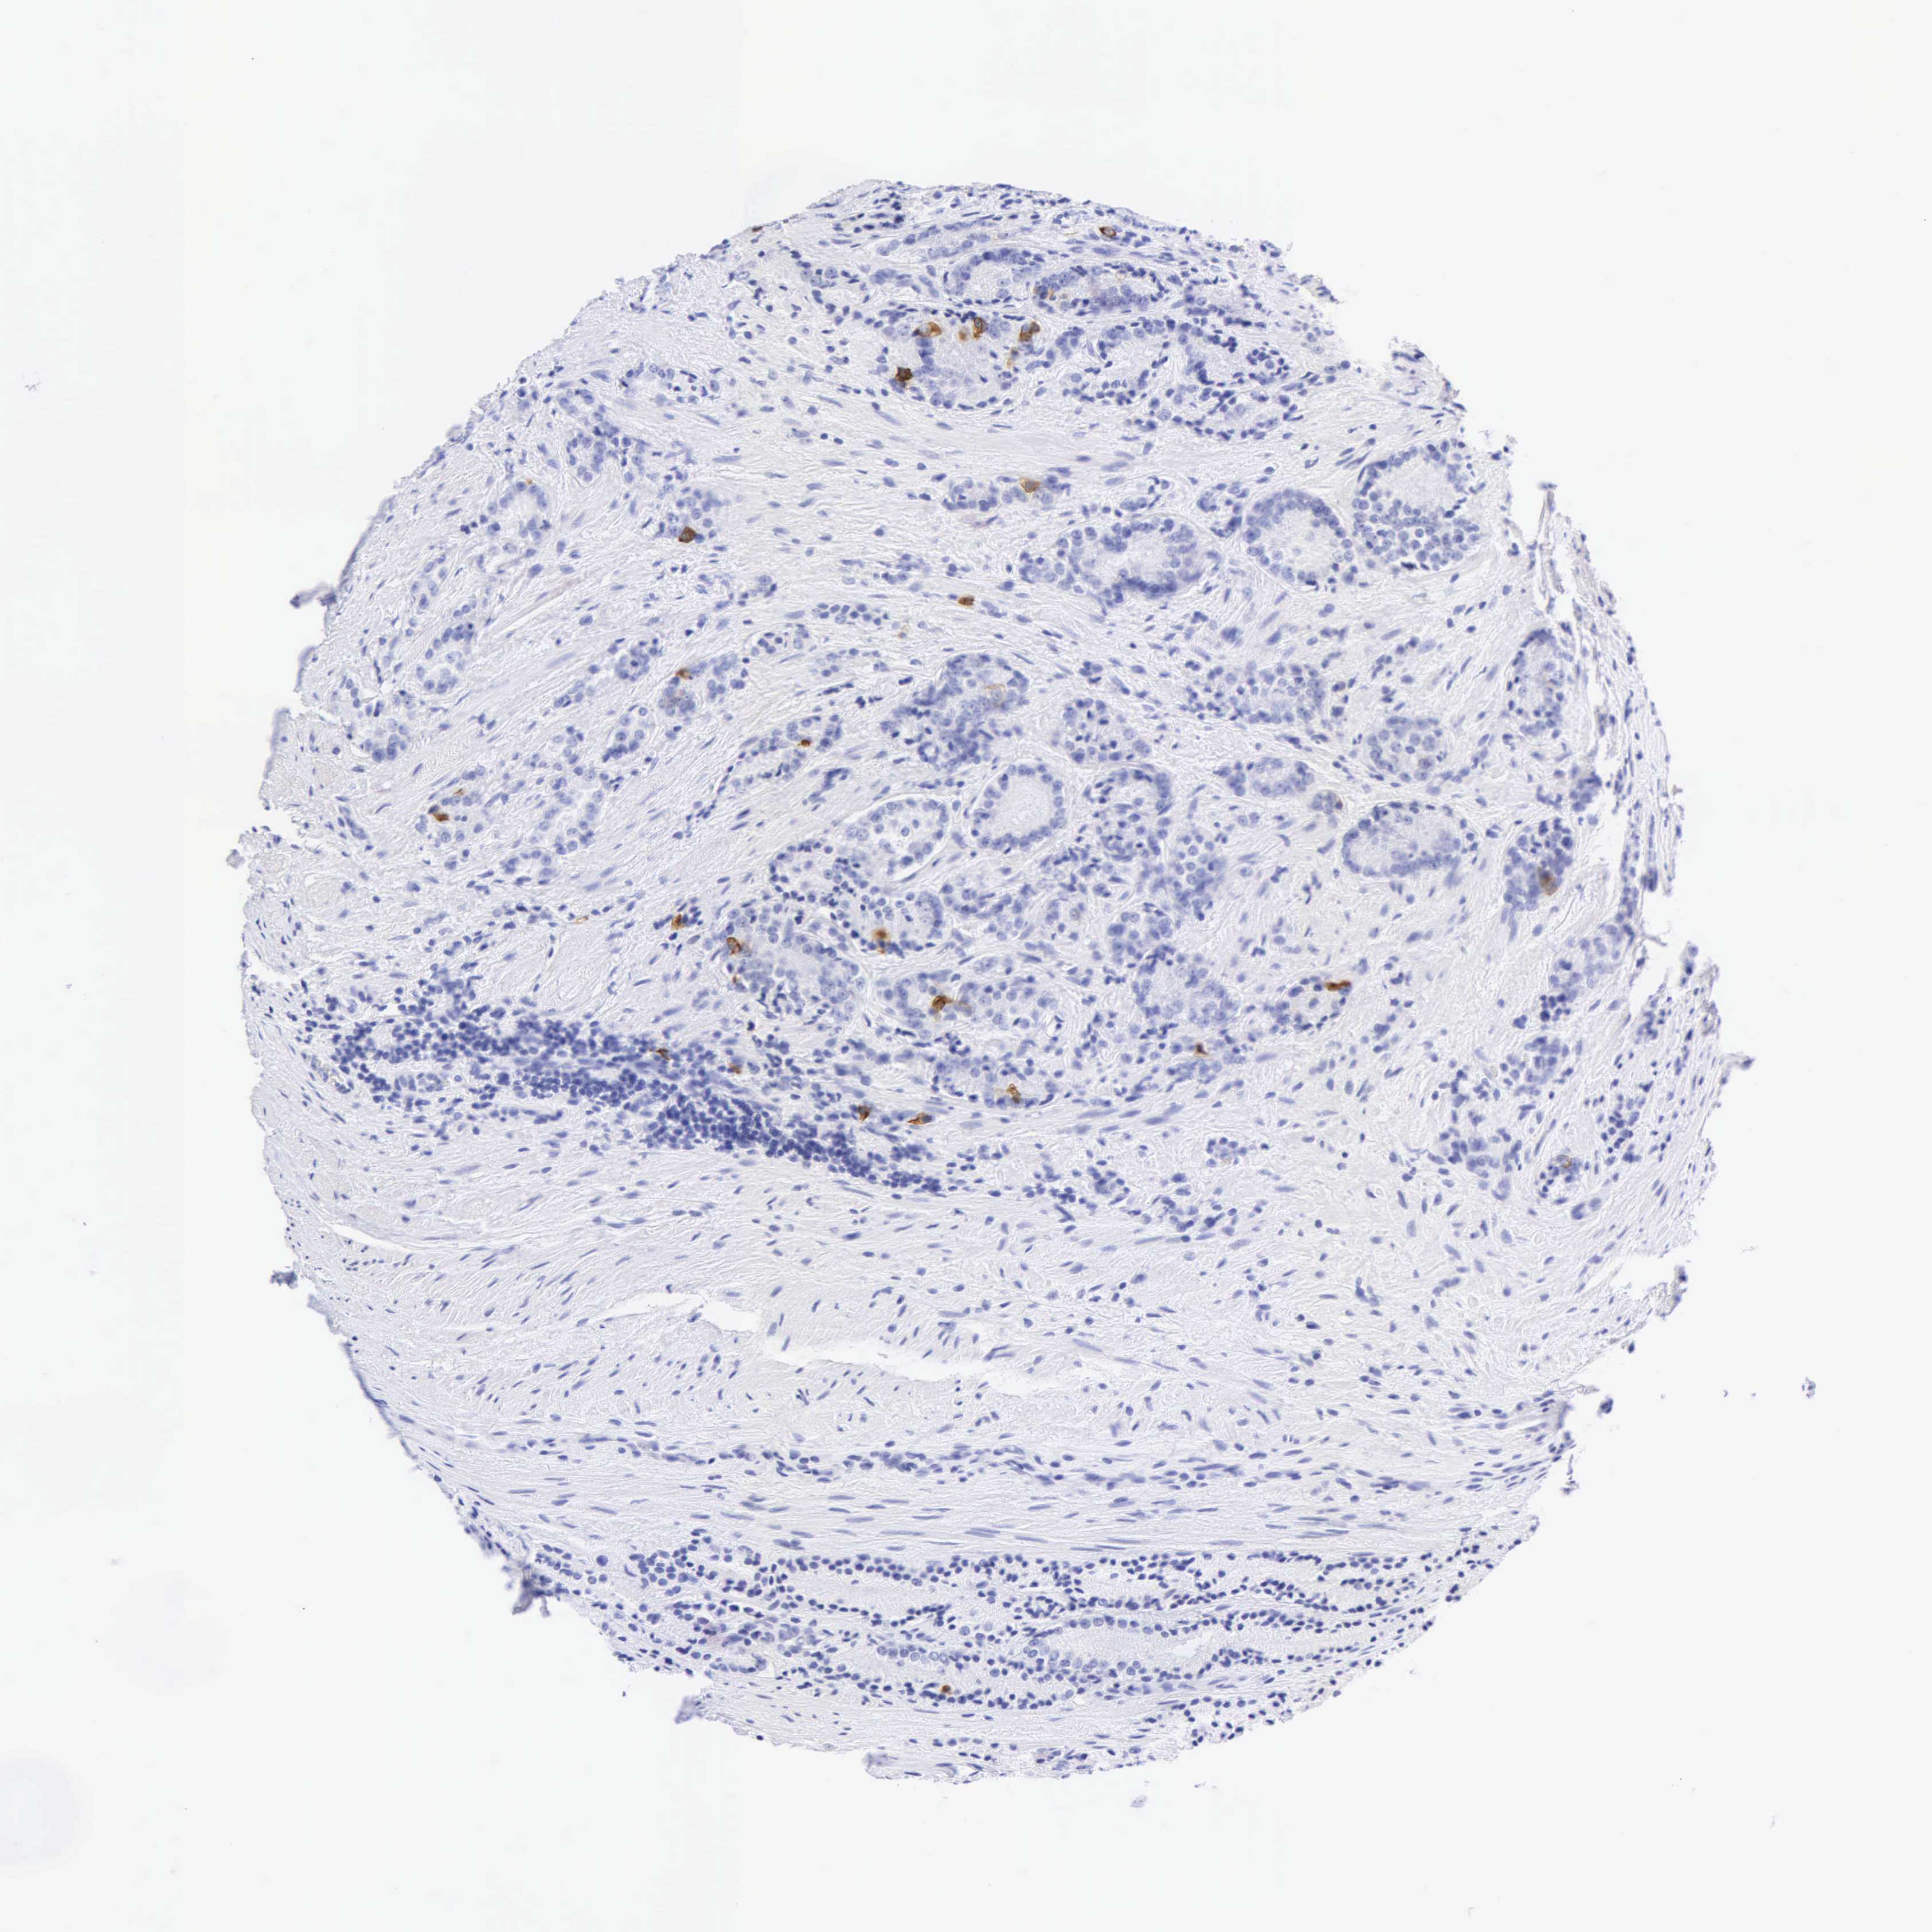

PROSTATE CANCER - Protein expressioni

A mouse-over function shows sample information and annotation data. Click on an image to view it in a full screen mode. Samples can be filtered based on level of antibody staining by selecting one or several of the following categories: high, medium, low and not detected. The assay and annotation is described here.

Note that samples used for immunohistochemistry by the Human Protein Atlas do not correspond to samples in the TCGA dataset.

Antibody stainingi

Antibody staining in the annotated cell types in the current human tissue is reported as not detected, low, medium, or high, based on conventional immunohistochemistry profiling in selected tissues. This score is based on the combination of the staining intensity and fraction of stained cells.

Each image is clickable and will lead to virtual microscopy that enables deeper exploration of all samples and also displays staining intensity scores, fraction scores and subcellular localization as well as patient and tissue information for each sample.

Antibody HPA024309

Antibody HPA024684

Antibody HPA027236

Antibody CAB000032

Adenocarcinoma, High grade

Adenocarcinoma, Low grade

Adenocarcinoma, Medium grade